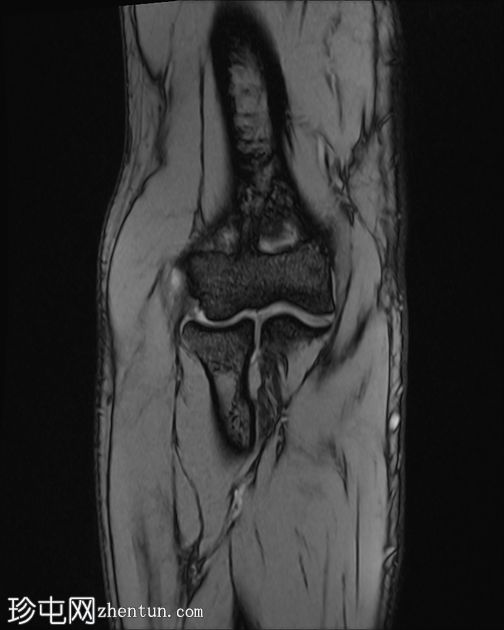

冠状位

STIR序列

梯度回波序列

肘关节伸肌总腱增厚,腱内可见高信号及部分撕裂。伴周围软组织水肿。

本病例展现了网球肘的典型

影像

学特征。